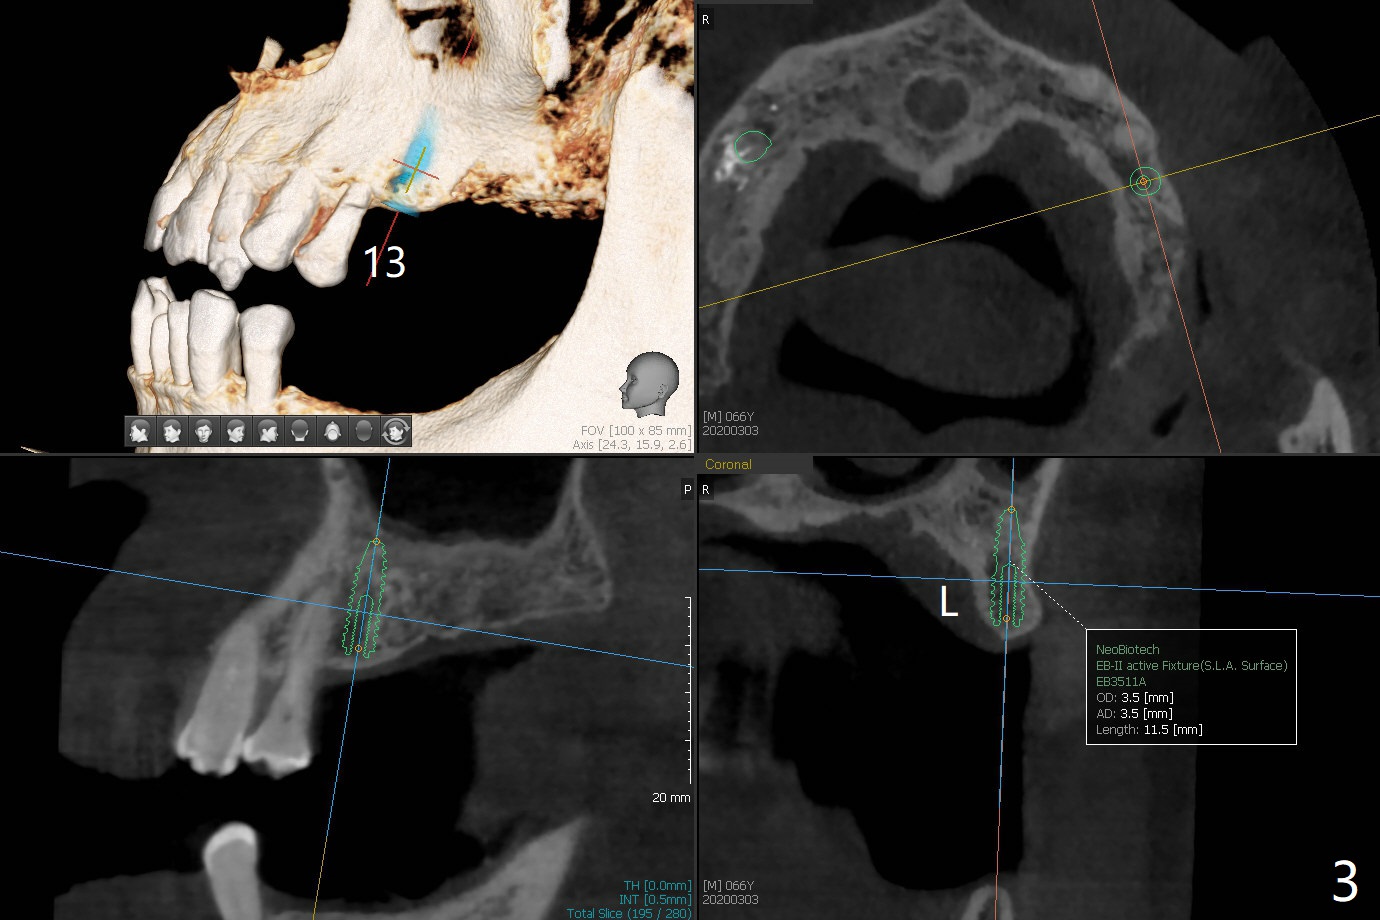

A 66-year-old man has lower RPD. Masti-cation is difficult due to #4 root fracture and #13 and 14 missing (Fig.1). After extraction of #4 with socket antibiotic treatment (Fig.2), finish #13 and 14 osteotomy and implant placement (Fig.3,4). Save auto-genous bone from #13, 14 and #4 using suction trap for #4 buccal gap closure.